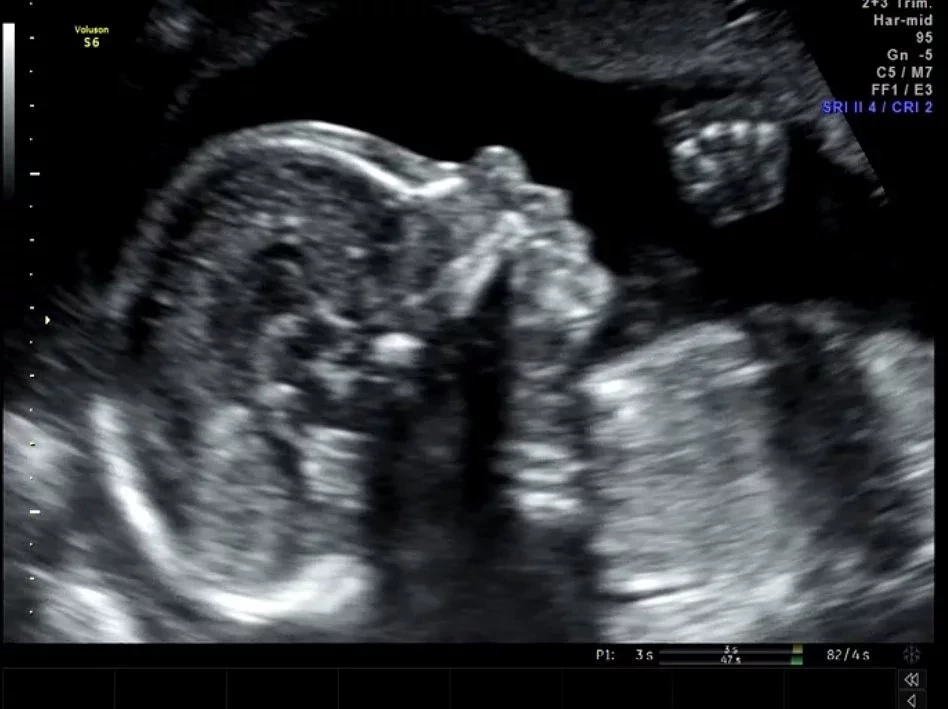

4. Seu filho, que ainda nem nasceu, tem mais de 200 mil seguidores no Instagram

Sim, Jake, na barriga da mãe Sammy, já é mais famoso que muita gente por aí.

Esse sou eu com 23 semanas (três semanas atrás). Papai e mamãe já revelaram meu nome no último vídeo do YouTube. Gostaram?Uma publicação compartilhada por  Jake (@jake.com) em